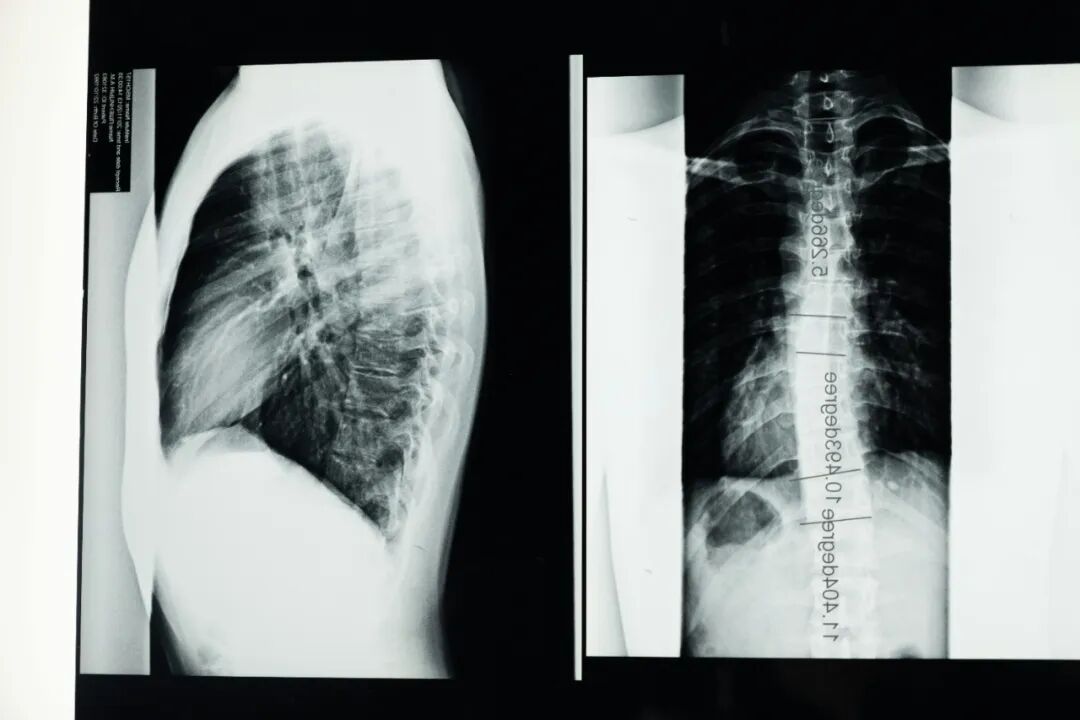

注意:五步筛查法当中只要有一步发现异常,都应尽快带孩子到医院或脊柱专科门诊检查拍摄全脊柱X光片进一步确诊。一旦确诊,应该及时、系统地治疗。

1、明确诊断:前往正规医院骨科或脊柱专科门诊就诊,拍摄X光片测量侧弯角度(10-20度为轻度、20-40度为中度、大于40度为重度)。